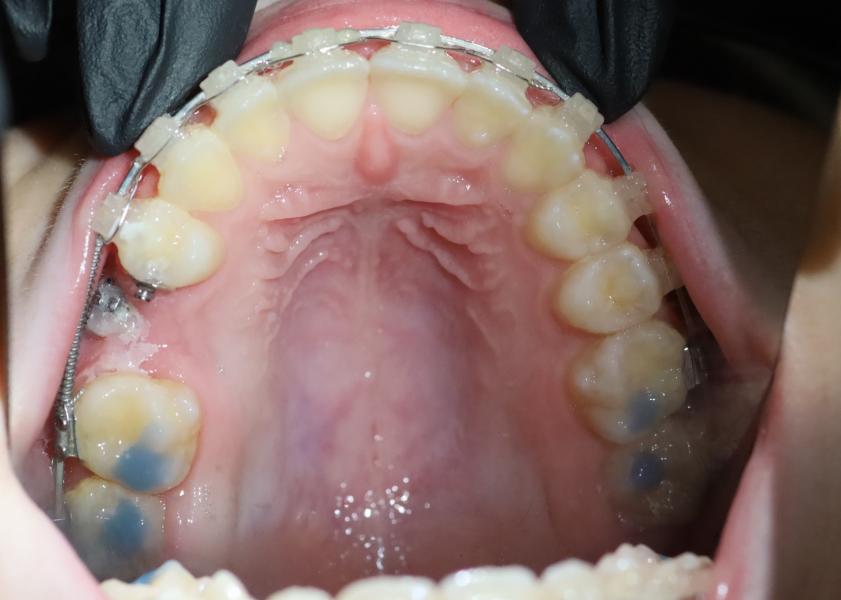

Удалили молочный зуб. Поставили брекеты для того, чтобы создать избыток места для зачатка постоянного зуба и ждали. Очень хотели, чтобы зачаток долгожданного зуба прорезался сам. Но спустя 6 месяцев ничего не произошло, зуб сам прорезаться не стал. И под контролем рентгена мы приняли решение сделать хирургический доступ к этому зачатку. И «насильно» стали тянуть его в нужном нам направлении.

Сейчас зуб (новый, который тянули) стоит в зубном ряду и функционирует! Ничего не угрожает здоровью соседнего зуба(шестерке). За шестеркой будем наблюдать. Должен прослужить долгие годы.